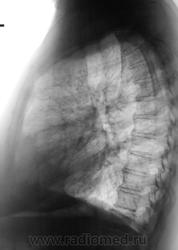

Пол пациента: Женский пол Тип патологии: Воспалительное заболевание неинфекционной природы Область исследования: Грудная клетка и верхние дыхательные пути Методы исследования: Rg Направлена на рентгенографию ОГК с подозрением на пневмонию https://radiomed.ru/sites/default/files/styles/case_slider_image/public/user/12/2.201201010021_0.jpg?itok=5JkVgdOr ID:31178 Пнд, 26/08/2013 - 17:26 #1 медсанчасть рег... Не на сайте Был на сайте: 11 лет 1 месяц назад Зарегистрирован: 11.06.2013 - 10:46 Публикации: 136 Да,можно предположить инфильтрацию S8 левого легкого,но не совсем чистые язычки. Пнд, 26/08/2013 - 17:41 #2 Kintire Не на сайте Был на сайте: 9 лет 6 месяцев назад Зарегистрирован: 25.02.2013 - 20:50 Публикации: 75 медсанчасть регион 12 wrote: Да,можно предположить инфильтрацию S8 левого легкого,но не совсем чистые язычки. +1. А слева корень не инфильтрирован? Пнд, 26/08/2013 - 20:39 #3 И.Бондаренко Не на сайте Был на сайте: 3 дня 10 часов назад Зарегистрирован: 13.09.2011 - 22:55 Публикации: 9206 Похоже, что и правая сторона задействована. Пнд, 26/08/2013 - 20:41 #4 Сергей Кузьминов Не на сайте Был на сайте: 1 год 1 неделя назад Зарегистрирован: 06.10.2012 - 15:51 Публикации: 11813 В любом случае ждать контроля,но синус передний слева уже нехорош. Втр, 27/08/2013 - 09:20 #5 Любовь С. Не на сайте Был на сайте: 9 лет 5 месяцев назад Зарегистрирован: 23.12.2010 - 01:58 Публикации: 2324 Избыточная прекардиальная клетчатка слева в диф.диагноз. "Предоставляя весь смысл и совершенство в распоряжение одного только Бога, вы избавляете себя от бездны хлопот." Джон Уитборн.

Да,можно предположить инфильтрацию S8 левого легкого,но не совсем чистые язычки.

+1. А слева корень не инфильтрирован?

Похоже, что и правая сторона задействована.

В любом случае ждать контроля,но синус передний слева уже нехорош.

Избыточная прекардиальная клетчатка слева в диф.диагноз.